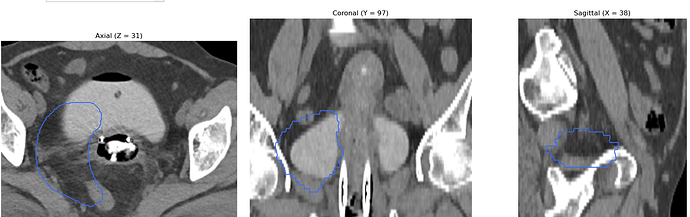

I am working on displaying CT images in the axial, coronal, and sagittal planes, along with dose maps and RTSTRUCT contours. While the CT and dose images are displayed correctly, I am having trouble overlaying the structures (contours) from the RTSTRUCT file on the CT images—the contours do not align properly with the CT, as shown in the attached image.